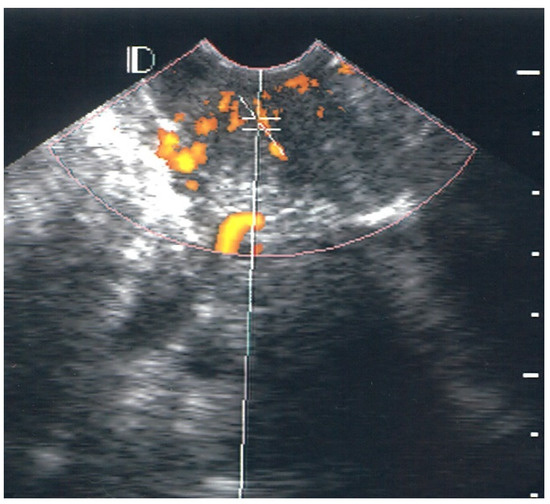

3.1. Visual Classification of Vascularity Findings on TV-PDU

| Classification | Numbers of Visualize Vascular Hotspots within Cervix (One Spot: 1 × 1 mm) |

|---|---|

| Class 0 | 0 |

| Class I | 1 to 5 |

| Class II | 5 to 10 |

| Class III | >10 |